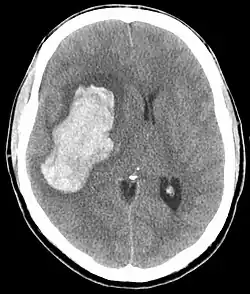

L'hypertension artérielle maligne est définie par une élévation importante de la pression artérielle s'accompagnant d'une souffrance viscérale (défaillance cardiaque, rénale, neurologique...) avec à l'examen du fond d'œil une rétinopathie hypertensive au stade III ou IV. Il s'agit d'une urgence médicale.

En général, les valeurs de pression artérielle systolique sont très élevées sans qu'il y ait de valeur seuil (200 à 300 mmHg), par contre en termes de diastolique, on retrouve des valeurs supérieures à 120 mmHg voire 130 mmHg. L'évolution ou les variations tensionnelles peuvent également être importantes.